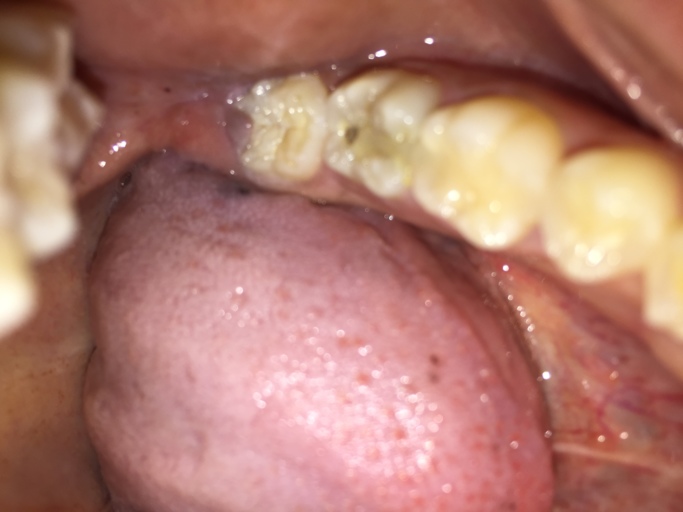

I have swelling in my cheek. I have pain in my tooth and under my gum I have a large bump which I causing the swelling I think and it hurts and I want to know what it is and if I need a root canal? In the photo it is the molar with filling that you...

Cavity or Something Else